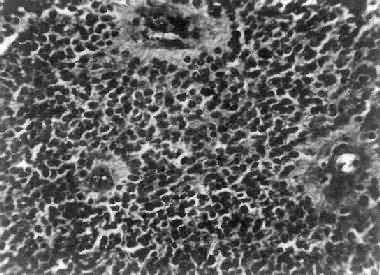

肉眼观,组织呈鱼肉状,色灰红。镜下,肿由圆形、椭圆形或胡萝卜形细胞构成,胞核着色深,胞浆少而边界不清楚,有多少不等的核分裂像。细胞密集,间质中有纤细的纤维,血管不多。细胞环绕一个嗜银性纤细的神经纤维中心作放射状排列形成典型的菊形团(图16-26),这对髓母细胞的病理诊断有一定的意义。细胞具有向神经元及神经胶质双向分化的潜能,既能向神经母细胞、节神经细胞分化,也能向胶质母细胞、星形胶质细胞分化。如细胞侵入软脑膜,可在蛛网膜下腔脑脊液中广泛播散转移。

图16-26 髓母细胞

细胞较小,着色深,密集排列,有菊形团形成